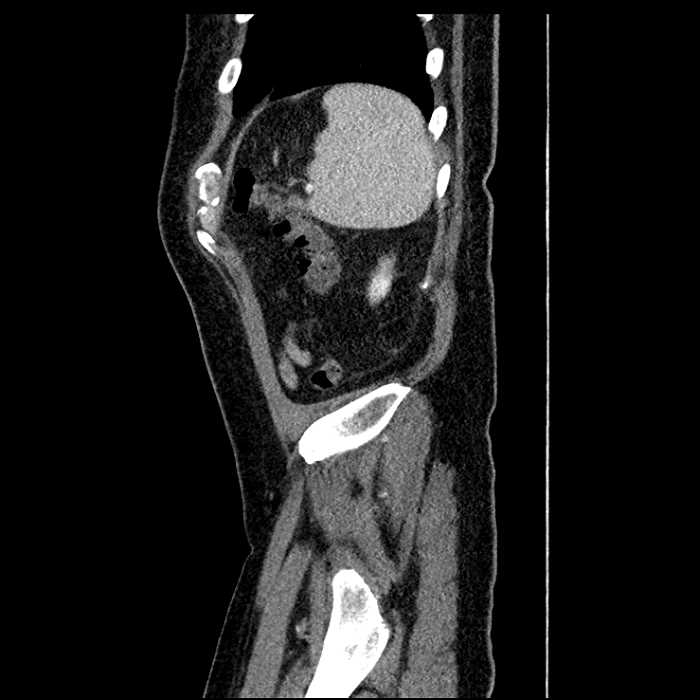

Age: 63

Sex: Male

Indication: Abdominal pain

• Large fluid density structure in hepatic segments 7 and 8 measuring 10 x 7 x 7 cm with internal septation and circumferential ill-defined low density compatible with edema

• Peripherally enhancing subcapsular collections along the anterior margin of the left hepatic lobe measuring 3 x 1 cm and 2 x 1 cm

• Clearly marginated fluid density structure in segment 7 and several other scattered tiny hypodensities, which likely represent cysts

• Hepatic abscess

Acute sigmoid diverticulitis complicated by a small contained perforation and a large abscess in the right hepatic lobe. Additional small subcapsular abscesses along the anterior margin of the left hepatic lobe.

• The classic CT imaging appearance is a double target sign with internal low density surrounded by an internal enhancing rim (capsule) and a low density external rim (edema)

• Abscesses may be unilocular or multilocular

• Gas is present in a minority of cases

Hepatic abscess showing the double target sign with low density internally surrounded by a thin inner enhancing rim (red arrow) and ill-defined outer low density rim (yellow arrow). Blue arrow indicates an internal septation. Red arrows: additional smaller subcapsular abscesses. Red arrow: focal contained perforation associated with diverticulitis.